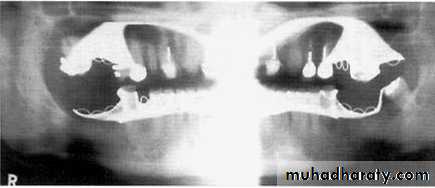

( hyoid bone, the hard palate, epiglottis).A dental panoramic tomograph showing the main real hard tissue shadows, including the plastic head support, drawn in on one side of the radiograph, NS — nasal septum,

MIT — middle and inferior turbinates, O — orbital margin, HP — hard palate, A — floor of antrum, Z — zygomatic arch, EAM — external auditory meatus, MP — mastoid process,

SP — styloid process, H — hyoid, P — plastic head support.

A dental panoramic tomograph showing the main real soft tissue and air shadows drawn in on

one side of the radiograph, NC — nasal cartilages, EL — ear lobe, SP — soft palate,DT — dorsum of tongue, Or — oropharnyx, NF — naso-labial fold, M — mouth.

A dental panoramic tomograph showing the main anatomical ghost or artefactual shadows drawn in on one side of the radiograph, PI — palate, Md — mandible, CV — cervical vertebrae.